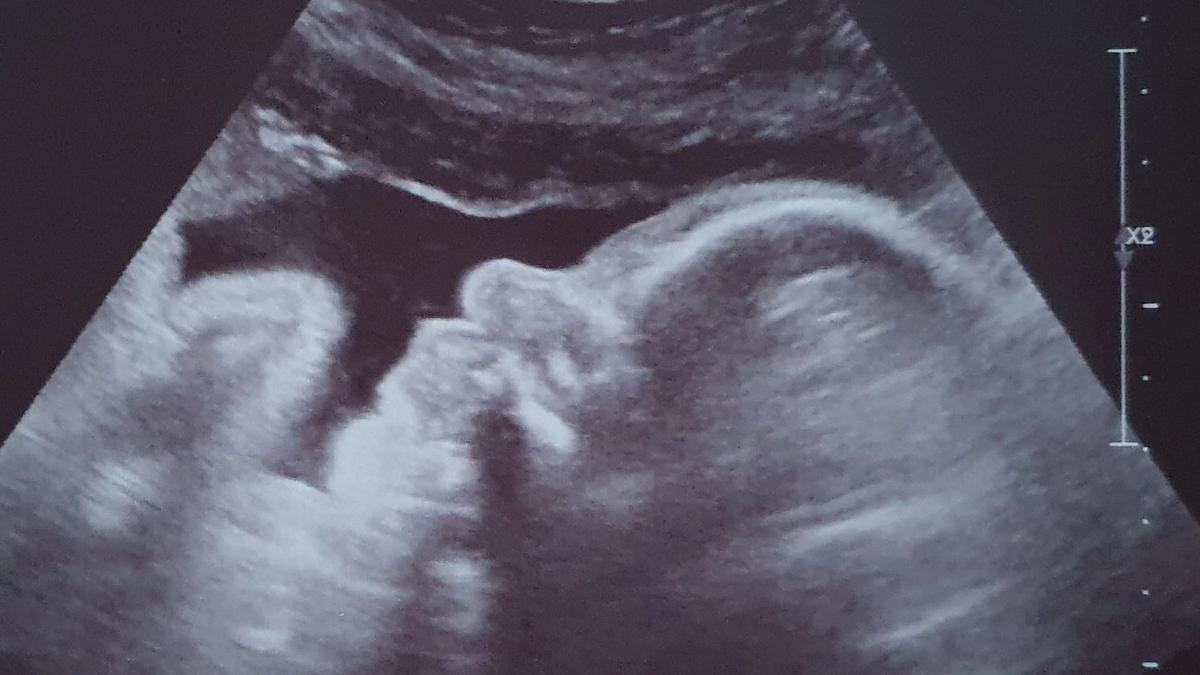

Vanaf dat moment kon ik nog alleen maar lachen. De weken vlogen voorbij en ook de 12 weken echo was goed. 29 augustus 2020 zou de datum zijn waar we naar uit mochten kijken en alles was goed. Iedereen mocht het weten en met de 20 weken echo wilden we weten wat het geslacht zou zijn. Dit werd al snel duidelijk, we kregen een dochter. Wat waren wij blij en alles was nog steeds goed. De weken vlogen voorbij, de buik groeide goed en ik pronkte er graag mee.

Ons meisje bleek aan de te kleine kant

Tot het een dag voor moederdag was en ik minder leven voelde. Ik belde wat onzeker de verloskundige en gaf aan dat het vast niks was, maar me toch wel zorgen maakte. De verloskundige kwam meteen langs. We hoorden een hartslag en mijn bloeddruk was goed. Ik was pas 24 weken dus dan kan het vaker voorkomen dat ze even wat rustiger zijn of anders liggen. Uit voorzorg werden we wel doorgestuurd naar het ziekenhuis voor een CTG en een echo. Eenmaal in het ziekenhuis maakten wij ons geen zorgen meer, want we hadden immers een hartslag gehoord. De CTG was goed, wel had de kleine een hoge hartslag en daarna kwam de echo. Tijdens de echo hoorden we dat er goede kindbewegingen waren, dus weer hadden we geen zorgen meer. Maar er werd wel gezegd dat ze aan de kleine kant was, haar beentje zit op de P6 lijn en P50 zou gemiddeld zijn. Dit was niet goed en ik moest de vrijdag erna terug komen voor een controle bij de gynaecoloog. Door Corona moest ik alleen komen en mocht mijn man helaas niet mee.

De gynaecoloog zei dat mijn man moest komen

Het was vrijdag 15 mei 2020 en ik ging naar de controle bij de gynaecoloog in het ziekenhuis. Vol goede moed ging ik erheen, want ik ben zelf ook klein dus maakte me al geen zorgen meer. “We krijgen gewoon een kindje wat niet zo groot is”, zei ik tegen mijzelf. Er werd een nieuwe groei-echo gemaakt. Hier werd verteld dat ze drie weken achter lag in groei. En dit was vreemd want tot de 20 weken echo groeide ze nog gewoon gemiddeld. De moed zakte in mijn schoenen en langzaam kreeg ik paniek. Er werd ook een dopplermeting gedaan (de doorbloeding van de navelstreng wordt dan gemeten). Ik kreeg te horen dat ik weer mocht gaan zitten en dat ze even alles in de computer ging zetten. Dit duurde voor mijn gevoel lang, heel lang… Vervolgens zei de gynaecoloog dat de dopplermeting niet goed was en dat het verstandig was dat mijn man direct zou komen. Ik werd doorgestuurd naar de afdeling en de kans was aanwezig dat ik werd opgenomen.